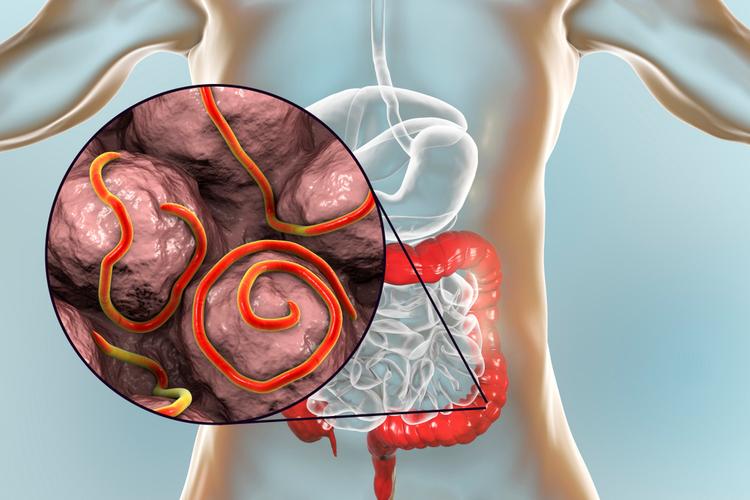

Giun kim là một loài ký sinh trùng nhỏ có thể sống trong ruột kết và trực tràng. Bạn sẽ nhiễm giun kim khi ăn phải trứng giun kim. Sau đó các quả trứng sẽ nở trong ruột. Trong lúc bạn ngủ, giun cái sẽ rời khỏi ruột và đến hậu môn để đẻ trứng ở vùng da quanh đó. Khi bạn đi ngoài mà không rửa tay kỹ, trứng giun có thể bám vào tay và lây lan sang người khác. Trứng giun có thể sống trên bề mặt đồ dùng sinh hoạt hằng ngày đến 2 tuần.

Nhiễm giun kim gây ra do một loại giun có tên gọi là Enterobius vermicularis có chiều dài khoảng bằng cái ghim dập giấy và thường lan truyền khi bạn chạm tay vào hậu môn sau đó chạm vào thức ăn hoặc các vật dụng sinh hoạt trong gia đình.